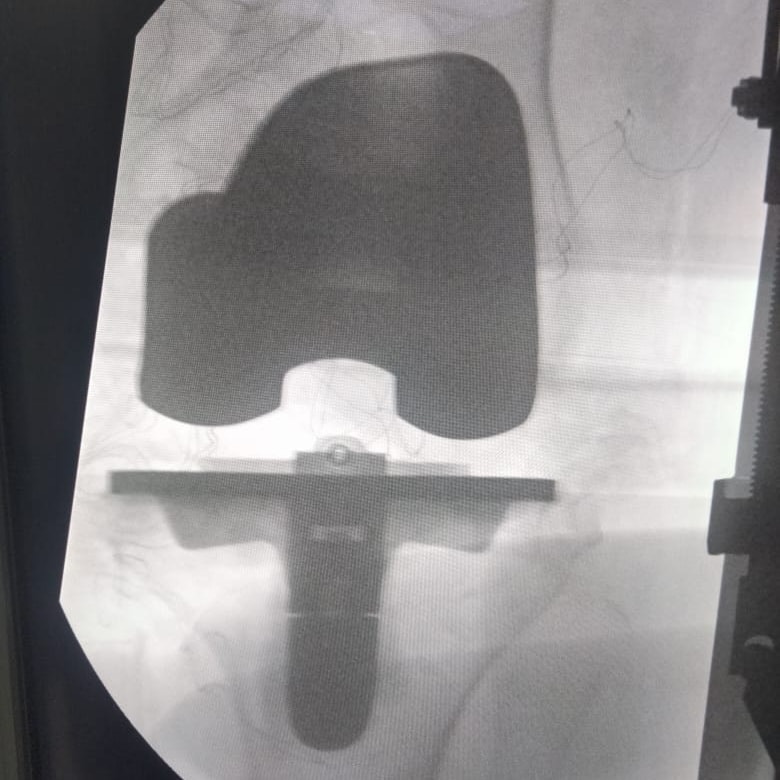

في إنجاز طبي جديد، نجح فريق جراحي بقسم جراحة العظام بمستشفى قها التخصصي، التابعة لأمانة المراكز الطبية المتخصصة، في إجراء أول عملية من نوعها لتغيير مفصل الركبة لسيدة تبلغ من العمر 71 عامًا، كانت تعاني من خشونة متقدمة وآلام حادة بالمفصل أدت إلى تيبسه ومنعتها من الحركة تمامًا.

وأوضح الدكتور كامل خالد، مدير المستشفى، أن الحالة تم استقبالها بقسم العظام، حيث خضعت للفحوصات والأشعة اللازمة، وتم عرضها على الفريق الطبي واستشاري جراحة العظام والمفاصل، ليُتخذ القرار بإجراء عملية تغيير مفصل الركبة باستخدام مفصل صناعي كامل أسمنتي.

وأضاف أن المريضة تم حجزها بالقسم الداخلي للعظام وتجهيزها للعملية التي أُجريت بنجاح، وخرجت منها بحمد الله في حالة مستقرة. وقد ترأس الفريق الجراحي الدكتور راشد حشاد، استشاري جراحة العظام والمفاصل، بمشاركة الدكتور سليمان غانم نائب جراحة العظام، وتحت إشراف الدكتور أشرف مبارك رئيس قسم العظام، والدكتور عبده محمد أخصائي التخدير، وبمساندة طاقم تمريض العمليات.

مفصل الركبة